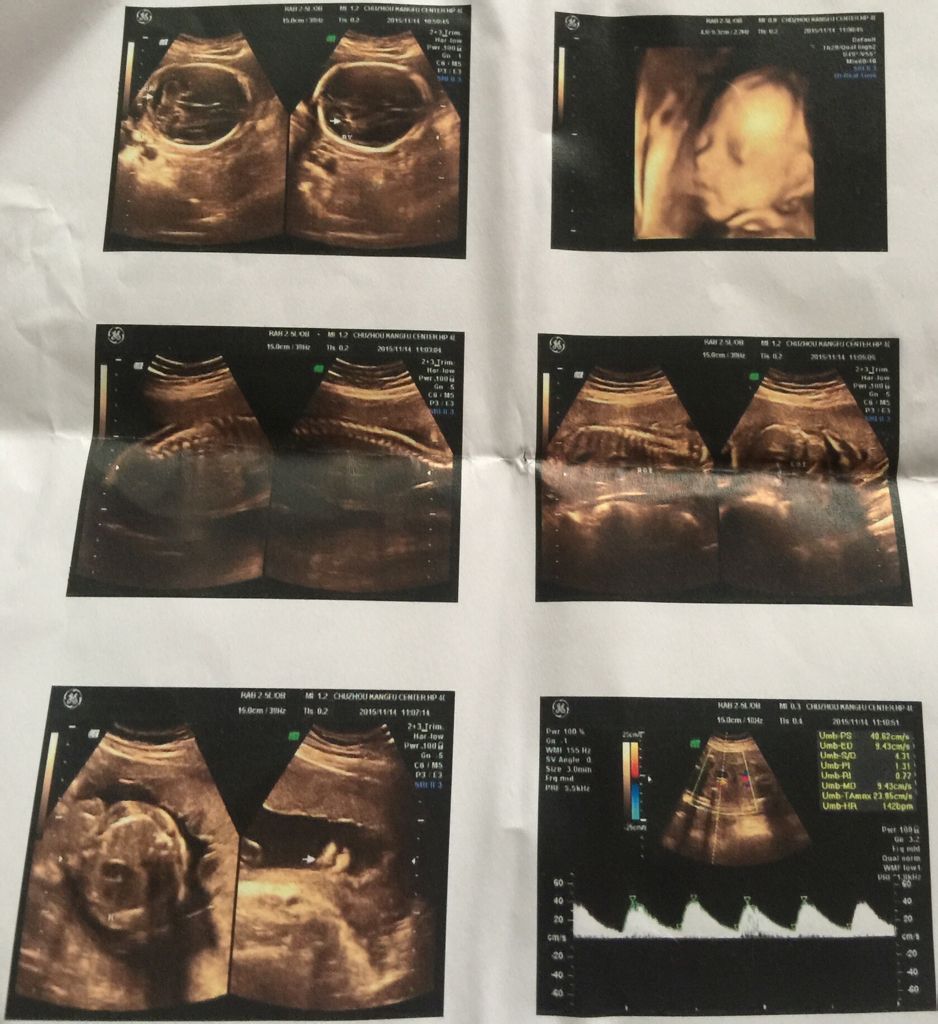

今天去做的四维彩超。医生说有五个半月了,可是说看不清手指和脚趾还有耳朵,让我七个半月再去复查。可是我看有的人彩超单上都有手臂腿和脚图片,为什么我的显示却没有,请懂的人帮忙看下,谢谢!

你好,四维超声检查的话旧沙浅,一般是比较细致的,建议在怀孕24周左右检查,而且怀孕5个多月,胎儿的大小应该是与怀孕时间是相符合的,建议孕期按时产检,在进入6个月后,胎儿的体掏吴泳以重和大小就会增加很快了。